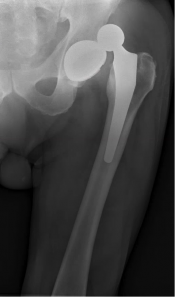

What’s the Diagnosis? Gepost op 1 juni 20181 juni 2018 door netwerkvsseh What’s the Diagnosis? @emdaily.cooperhealth.org Dit delen: Delen op X (Opent in een nieuw venster) X Share op Facebook (Opent in een nieuw venster) Facebook Delen op LinkedIn (Opent in een nieuw venster) LinkedIn E-mail een link naar een vriend (Opent in een nieuw venster) E-mail Afdrukken (Opent in een nieuw venster) Print Vind-ik-leuk Aan het laden... Gerelateerd